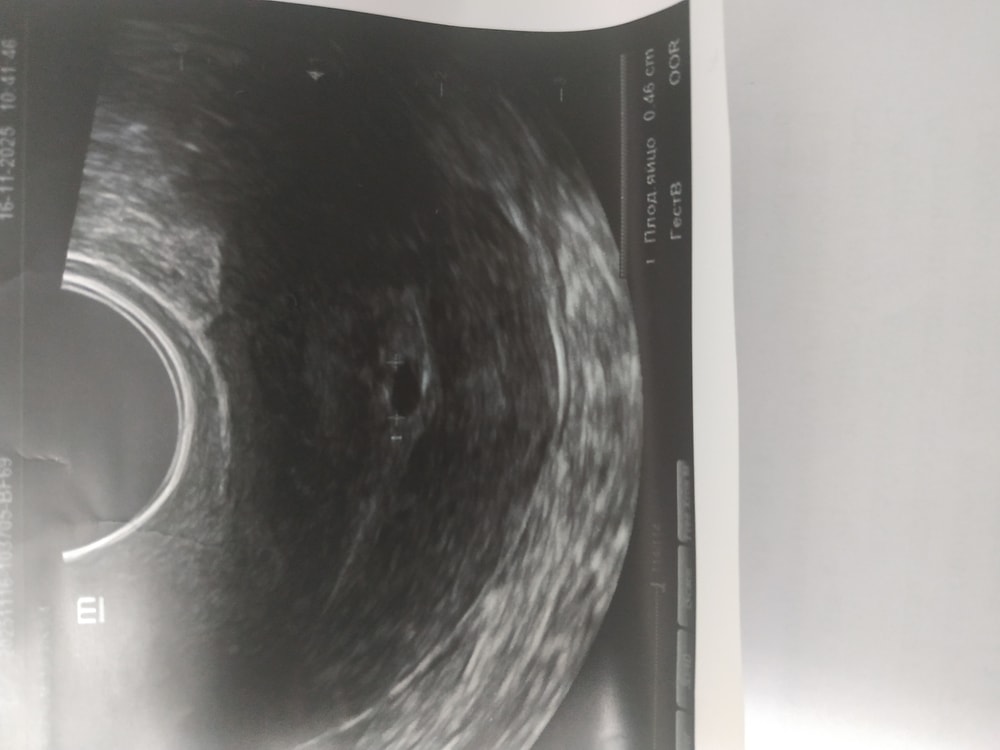

Изображениевот снимок УЗИ с пя.

Катэ, посмотрите пожалуйста, я добавила снимок с последнего УЗИ. Да, я поняла иду завтра к гинекологу. Ничего не предпринимаю из самодеятельности.

Василисса, спасибо за то что поделились вашим случаем. Тоже перебирая возможные варианты подумала, а вдруг не пя. Но в моем случае оно растет. Было 7 ноября 3 мм, 16.11 - 4,6мм. Это что-то растет хоть и маленькими темпами.

Вакуум или таблетка .3 месяца и пробуете заново . Чистка на более позднем сроке . Плодное яйцо есть , а эмбриона скорее всего нет вообще . И дурье не майтесь , а то потом жалеть будете . Должно было бы выйти само - вышло, у вас сидит , тянуть нельзя.